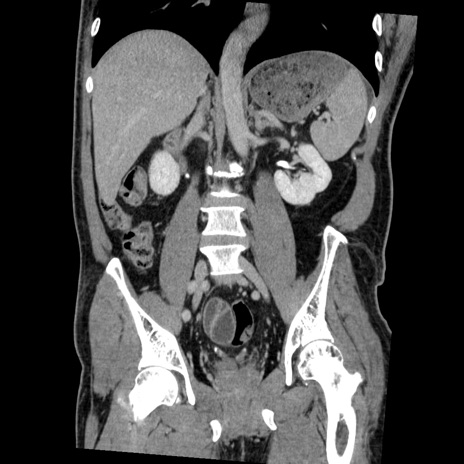

症例22(冠状断像)

【症例】50歳代男性

【主訴】腹痛

【現病歴】AVMからの被殻出血のため回復期リハ病棟入院中。 本日午後3時頃急に下腹部痛が出現した。

【既往歴】AVM、被殻出血、虫垂炎、高血圧

【身体所見】意識晴明、左半身不全麻痺、会話の理解は良好、36.5°C、腹部:膨隆、全体に板状硬、下腹部正中に圧痛点あり、反跳痛-、筋性防御不明、右下腹部にope scar

【データ】WBC 9400、CRP 0.06